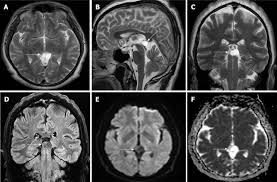

The diagnosis of pineal cyst is usually established by MRI with defined radiological criteria to distinguish benign pineal cyst from tumors of this area. A pineal cyst is usually only treated if it causes symptoms. In order to detect the presence of a cystic mass in the head magnetic resonance imaging is required.

Brain Magnetic Resonance Imaging Mri Of A 40 Year Old Patient Showing Download Scientific Diagram